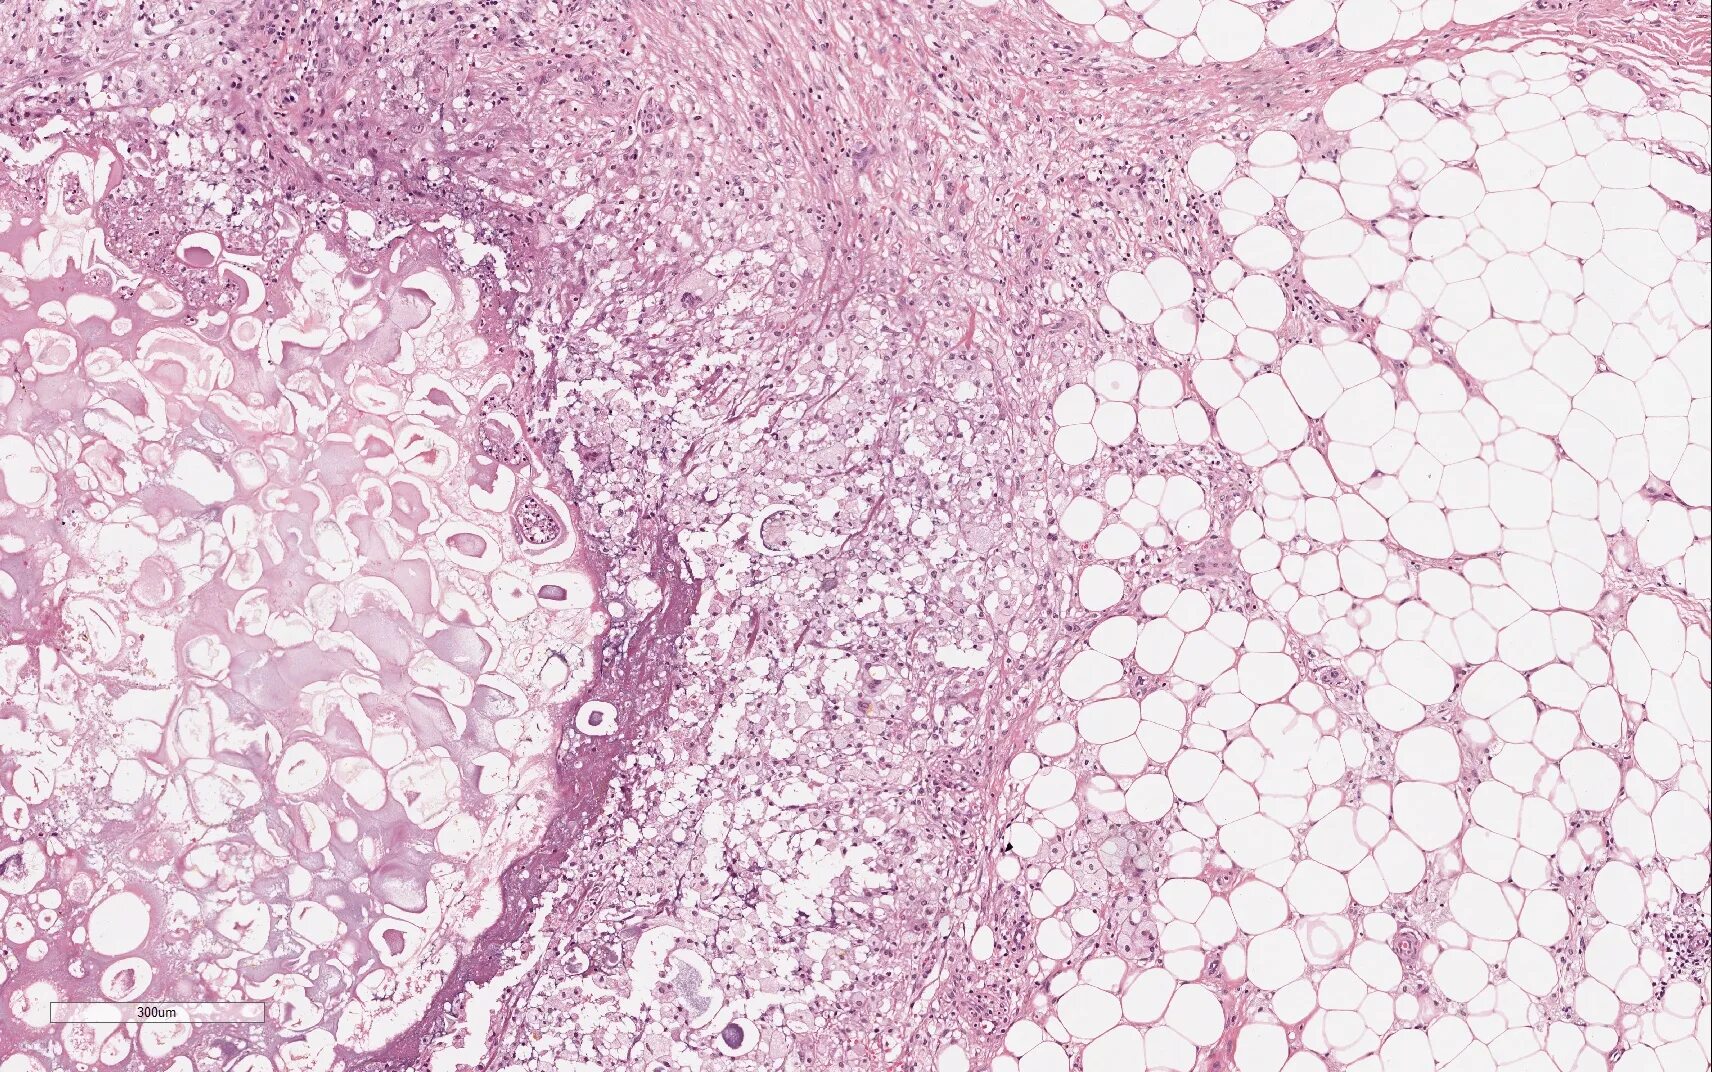

Гистологическое исследование полипа